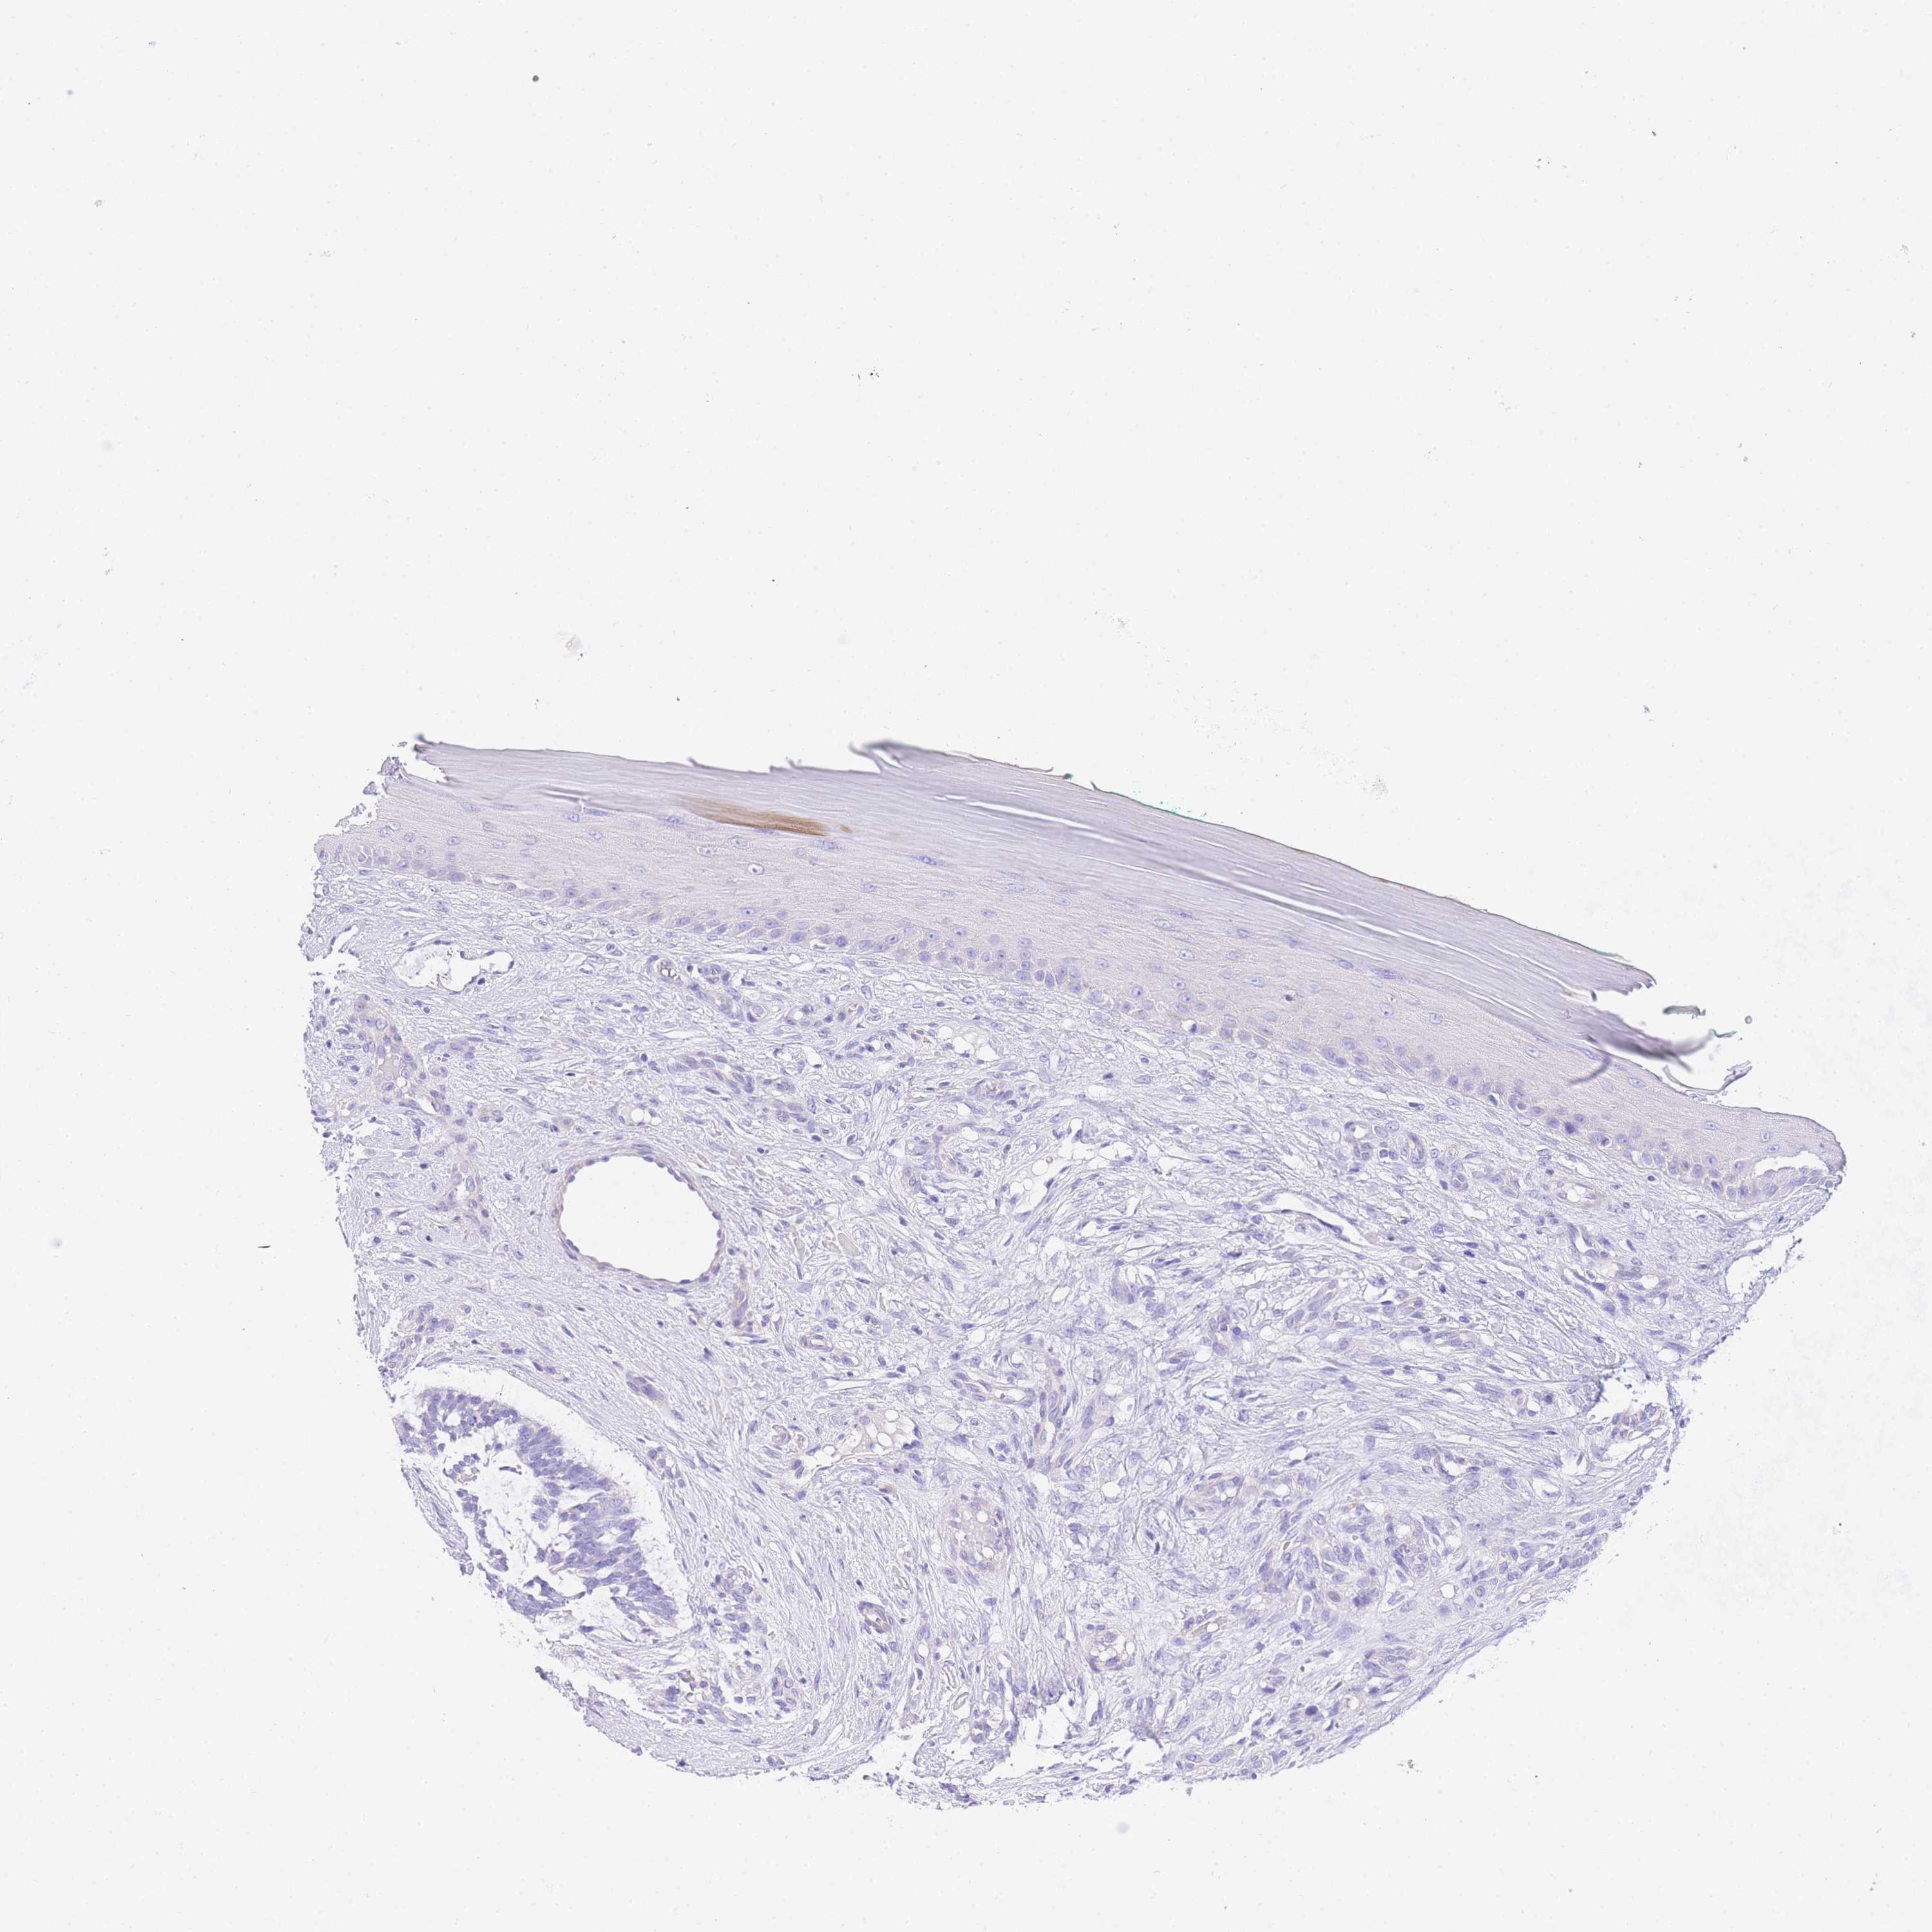

Basal cell and squamous cell cancer

SKIN CANCER - Protein expressioni

A mouse-over function shows sample information and annotation data. Click on an image to view it in a full screen mode. Samples can be filtered based on level of antibody staining by selecting one or several of the following categories: high, medium, low and not detected. The assay and annotation is described here.

Each image is clickable and will lead to virtual microscopy that enables deeper exploration of all samples and also displays staining intensity scores, fraction scores and subcellular localization as well as patient and tissue information for each sample.

Antibody HPA049809

Basal cell carcinoma

Squamous cell carcinoma, NOS

Squamous cell carcinoma, metastatic, NOS